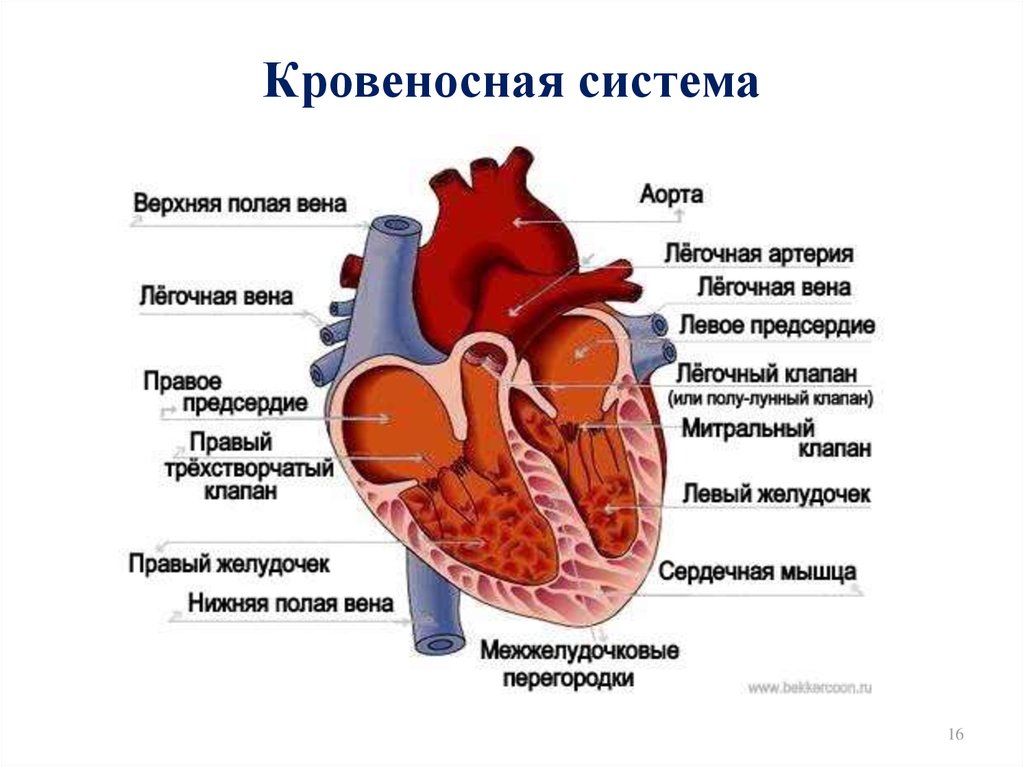

Кровеносная система человека: структура и функции